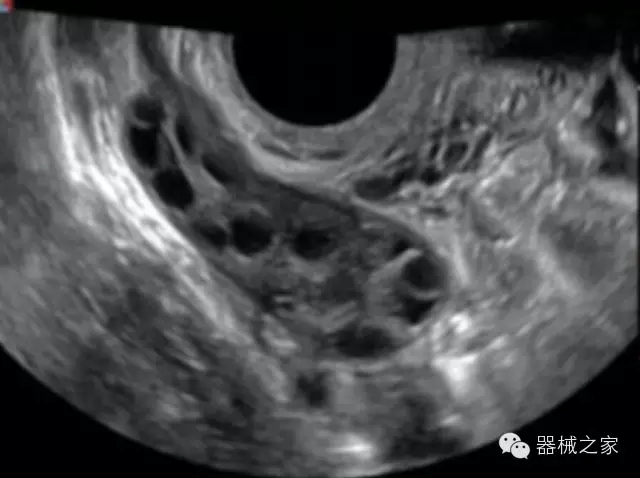

臨床圖片賞析

·更高的HQ羊膜腔鏡成像技術(shù)精細(xì)觀察每一個(gè)暗區(qū)細(xì)節(jié);

·亞陣元技術(shù):獨(dú)有的亞陣元技術(shù),對(duì)獨(dú)立晶片做二次切割,減少旁瓣偽像,增加臨床診斷的準(zhǔn)確性;

·μ-Scan微米成像技術(shù):開立獨(dú)有的μ-Scan技術(shù),還原出真實(shí)細(xì)膩、層次對(duì)比優(yōu)異的二維圖像;

·倒相諧波成像技術(shù):倒相諧波技術(shù)在去除基波信號(hào)的基礎(chǔ)上獲取兩倍二次諧波信號(hào),提高組織圖像的對(duì)比分辨力;

·智能微血流成像技術(shù):智能微血流捕捉技術(shù)可以提取出隱藏在背景噪聲中的弱血流信號(hào),大大提高低速血流的敏感性;